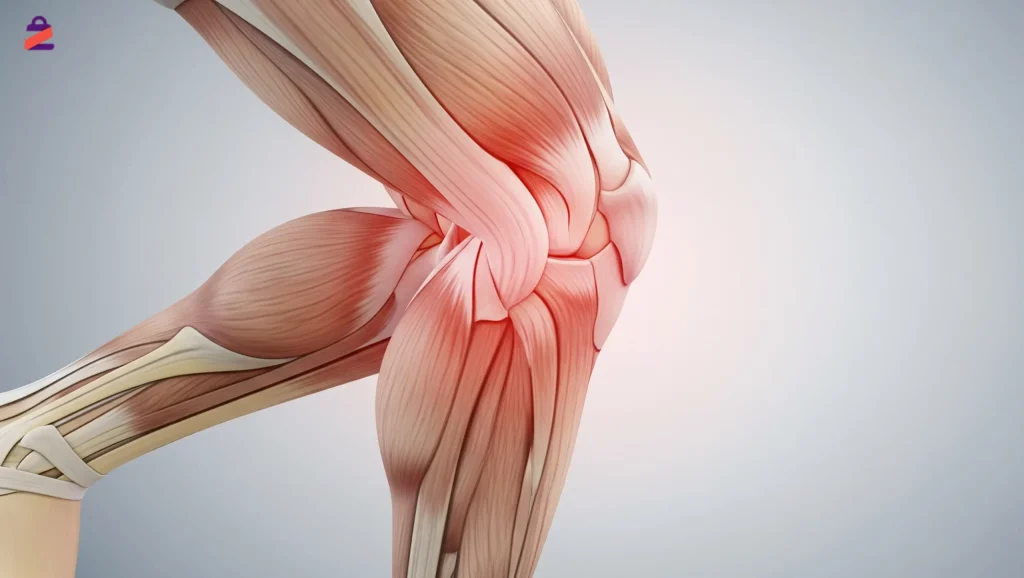

شوددرد زانو هنگام خم شدن یکی از مشکلات شایع میان افراد در سنین مختلف است که میتواند فعالیتهای روزمره مانند نشستن، بالا رفتن از پلهها یا حتی نماز خواندن را با اختلال مواجه کند. این درد ممکن است به دلایل مختلفی از جمله التهاب، آسیبهای ورزشی یا فرسودگی مفصل زانو ایجاد شود.

زانو درد هنگام خم شدن معمولاً نشاندهنده مشکلی در ساختارهای داخلی یا اطراف مفصل زانو است. از غضروفها و رباطها گرفته تا تاندونها و بافتهای نرم اطراف مفصل، همگی ممکن است تحت تأثیر فشار، التهاب یا آسیب قرار بگیرند. در ادامه به رایجترین دلایل این نوع درد اشاره میکنیم: